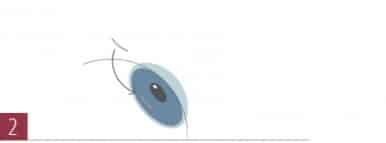

Der Ring wird im zweiten Schritt in diesen Tunnel eingeschoben und exakt positioniert.

Der Ring wird im zweiten Schritt in diesen Tunnel eingeschoben und exakt positioniert.